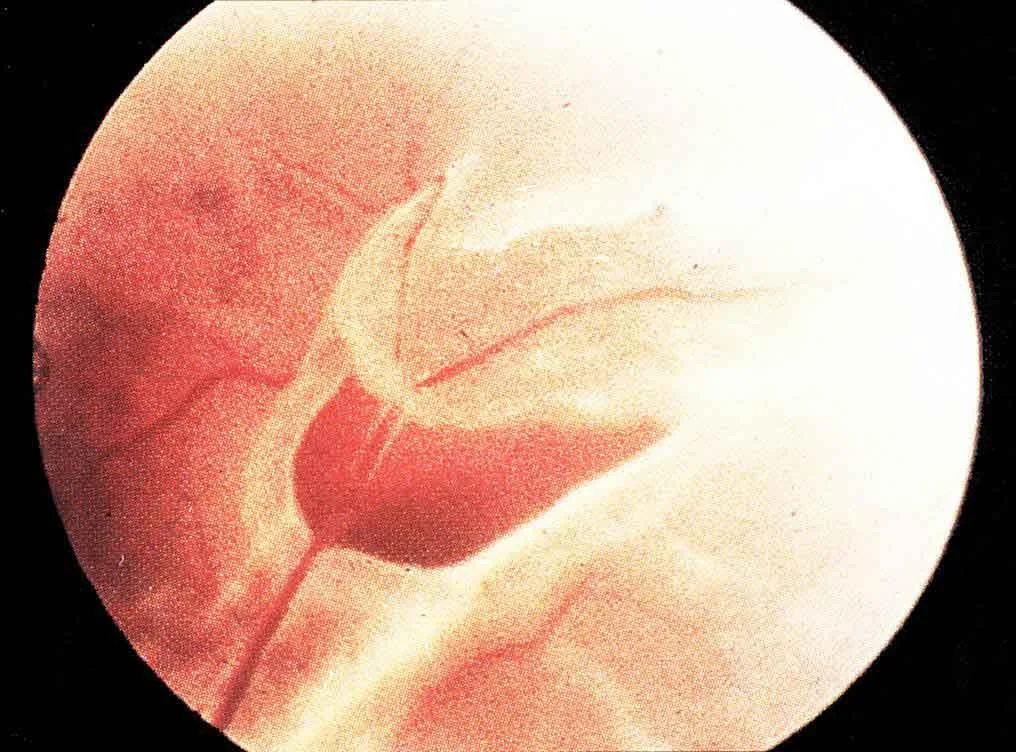

Rhegmatogenous Retinal Detachment Formation

- Clinical manifestation:

- Flashes of light, floaters, a curtain or shadow moving over the field of vision, peripheral and/or central visual loss.

- Elevation of the retina and a flap tear or break in the retina